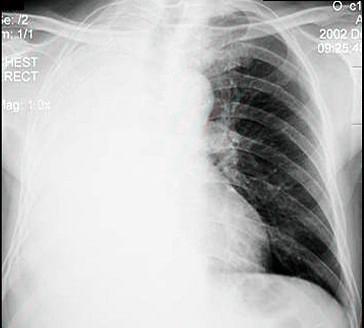

- 单项选择题男性患者,65岁, 因胸痛1个月就诊,胸片检查见图, 以下诊断中最明确的是 ( )

A、右肺炎症

B、右侧胸腔积液

C、右肺不张

D、肺栓塞

E、右肺胸膜肥厚